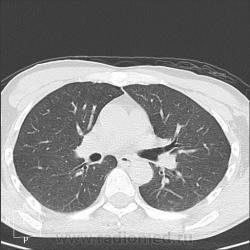

Пациент 46 лет поступал с комой неясного генеза. Выполнена КТ головного мозга и легких. Выявлено массивное субарахноидальное кровоизлияние с прорывом в желудочки. Улучшение неврологической симптоматики в процессе лечения, сохранение нарушения глотания. Через неделю появилась фебрильная t, кашель с мокротой.

К развитию аспирационной пневмонии.

Ну да, похоже на то)